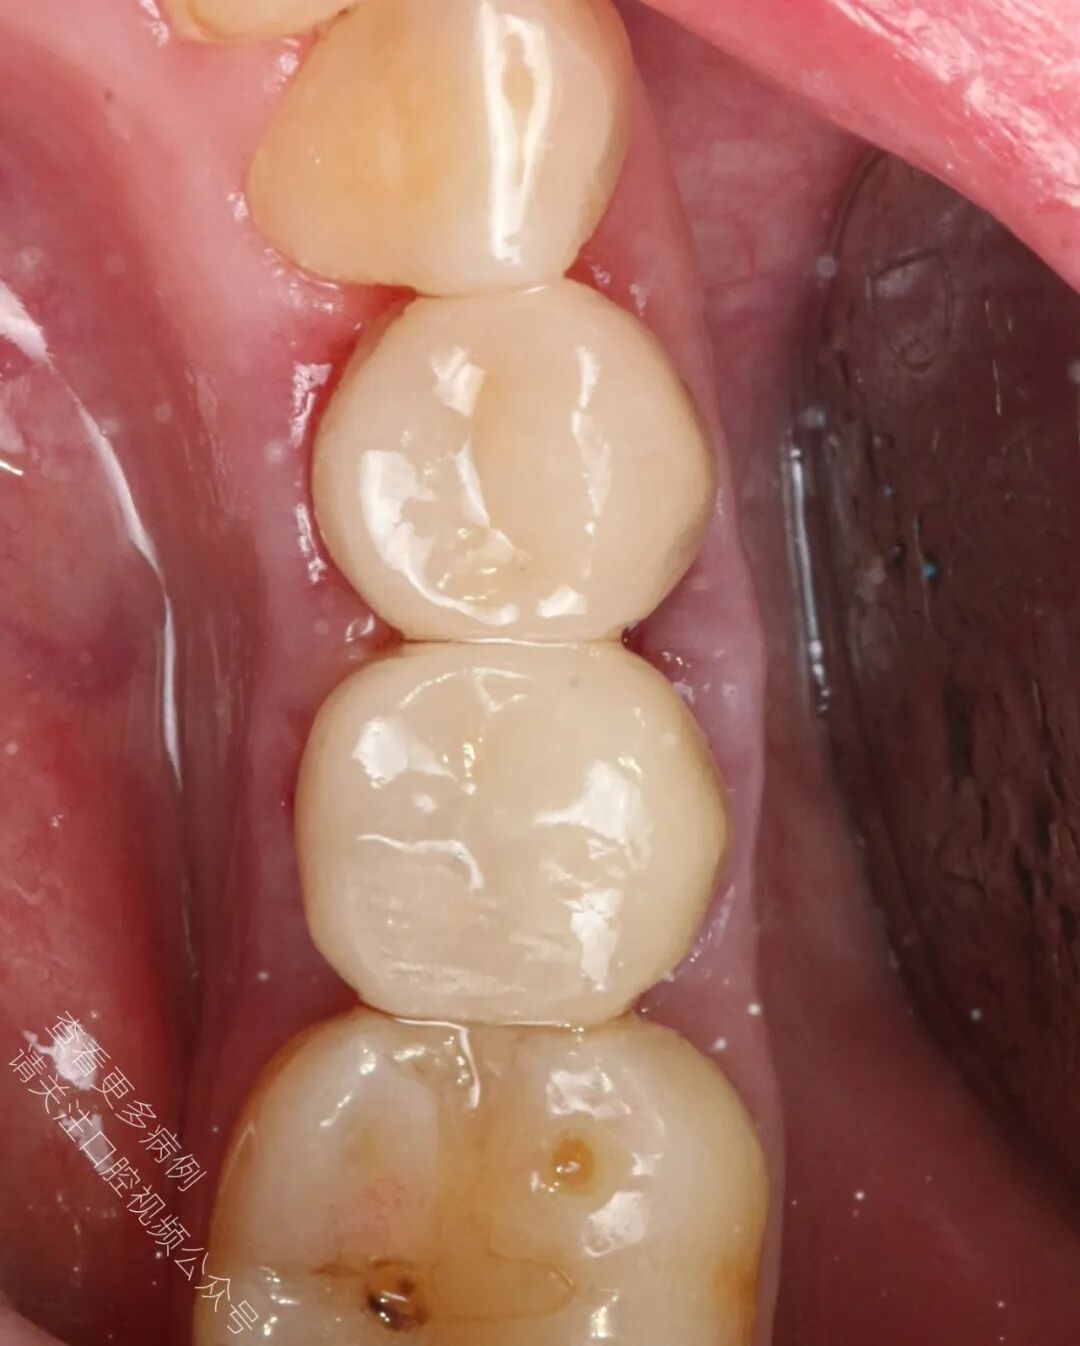

🪄 冠修复体制作完成后返回诊所,在隔离环境下完成粘接

🪄 术后X光片显示冠修复体边缘密合良好,修复效果理想